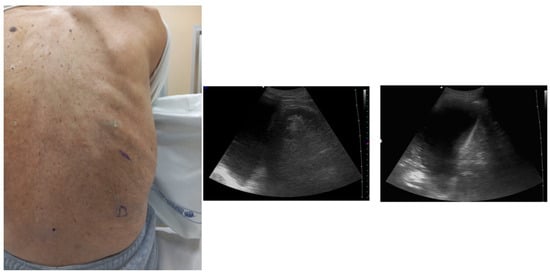

7. Ultrasound-Guided Thoracentesis